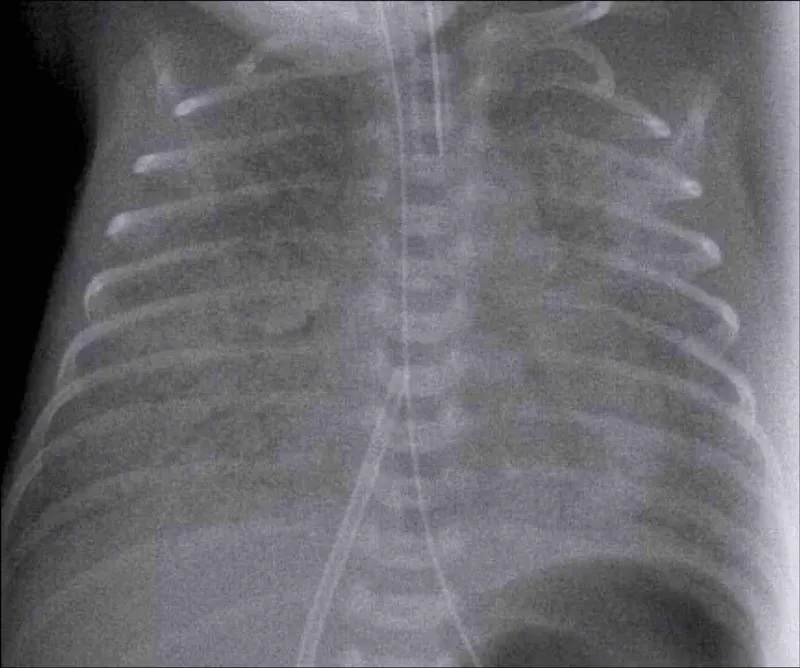

- Neonatal Respiratory Distress Syndrome (NRDS): Surfactant deficiency in premature infants (born < 35 weeks gestation) due to immature Type II pneumocytes.

- Pathophysiology: ↓ Surfactant → ↑ alveolar surface tension → widespread atelectasis (alveolar collapse) → ↓ lung compliance & functional residual capacity (FRC) → V/Q mismatch & severe hypoxemia.

- Clinical Findings: Presents within minutes to hours of birth with tachypnea, expiratory grunting, and nasal flaring.